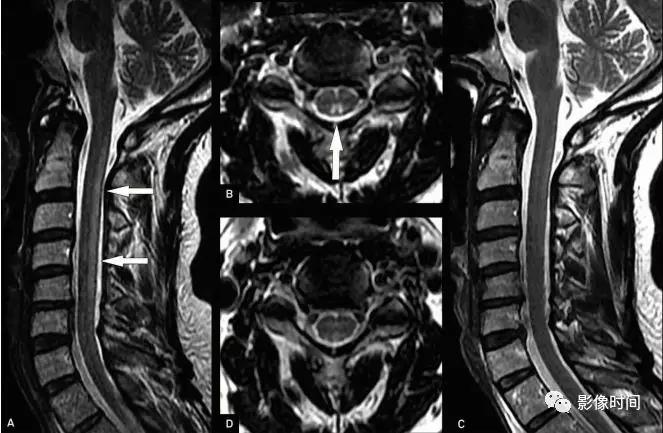

MRI:

-

矢状位 T2WI 发现长节段高信号

矢状位 T2WI 脊髓周围流空低信号血管影

部分可见强化,提示血脑屏障破坏

脊髓内长节段T2WI高信号,髓周可见多发点状流空血管,增强扫描出现强化

脊髓长节段病灶,中心分布为主,T2WI高信号,注意椎体T1出现高信号

病灶分布于脊髓后索,T2WI高信号